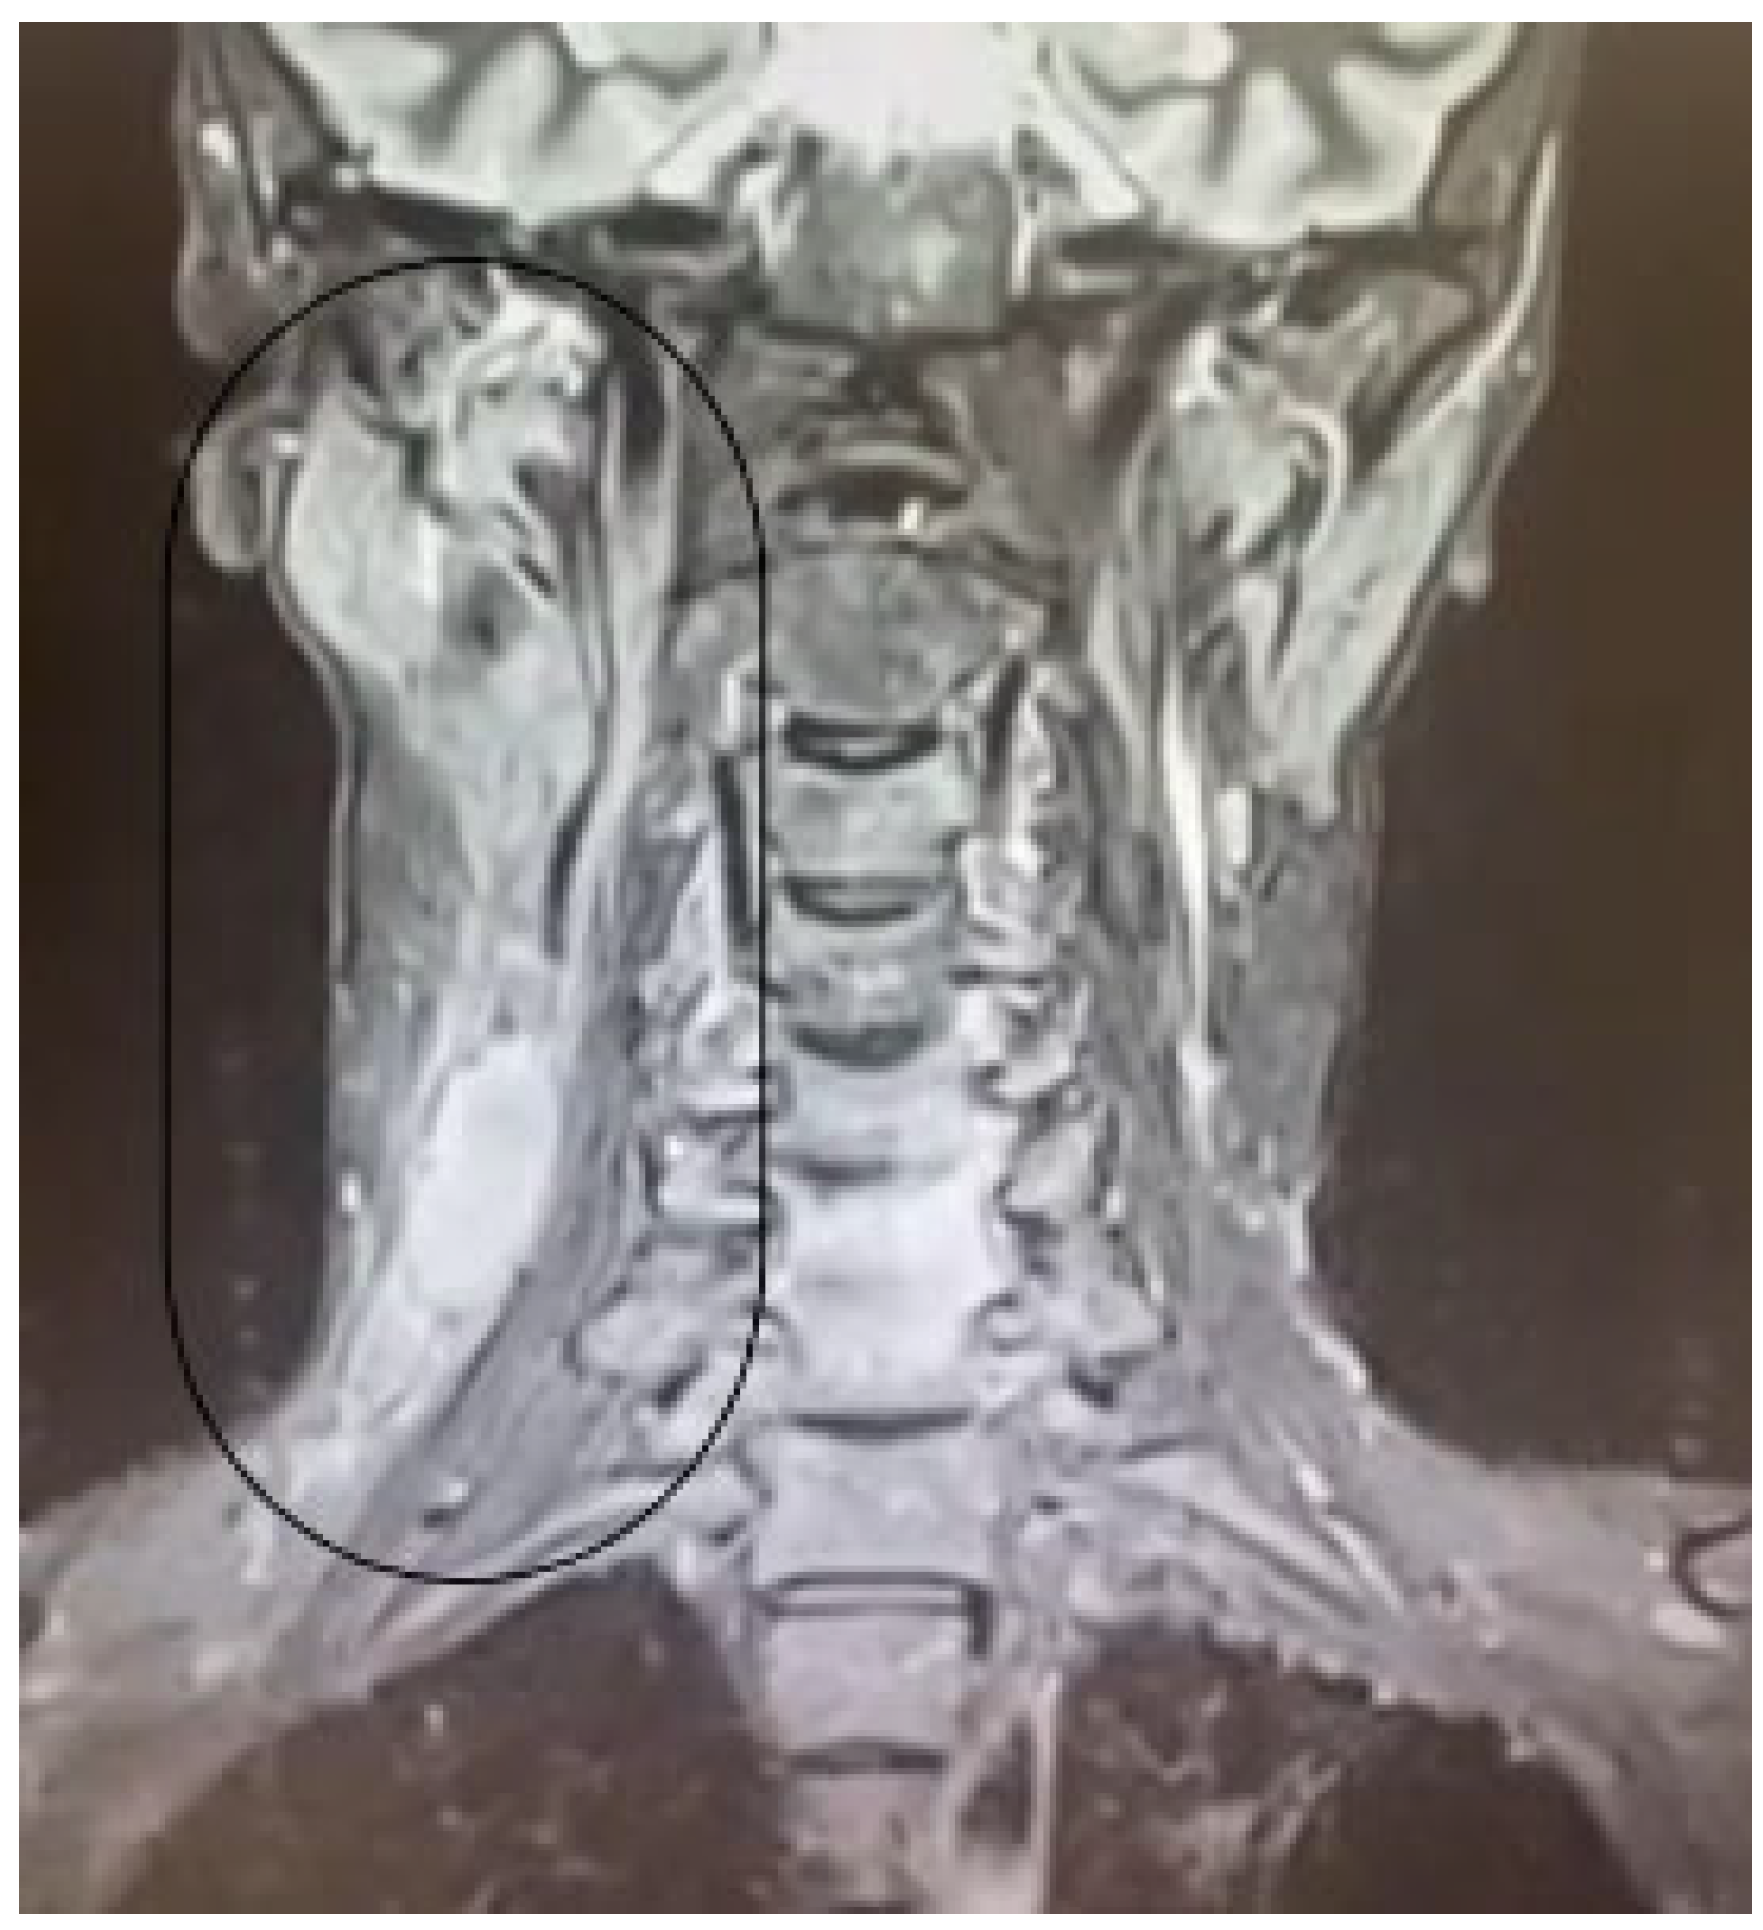

2.3.3. Imaging Findings